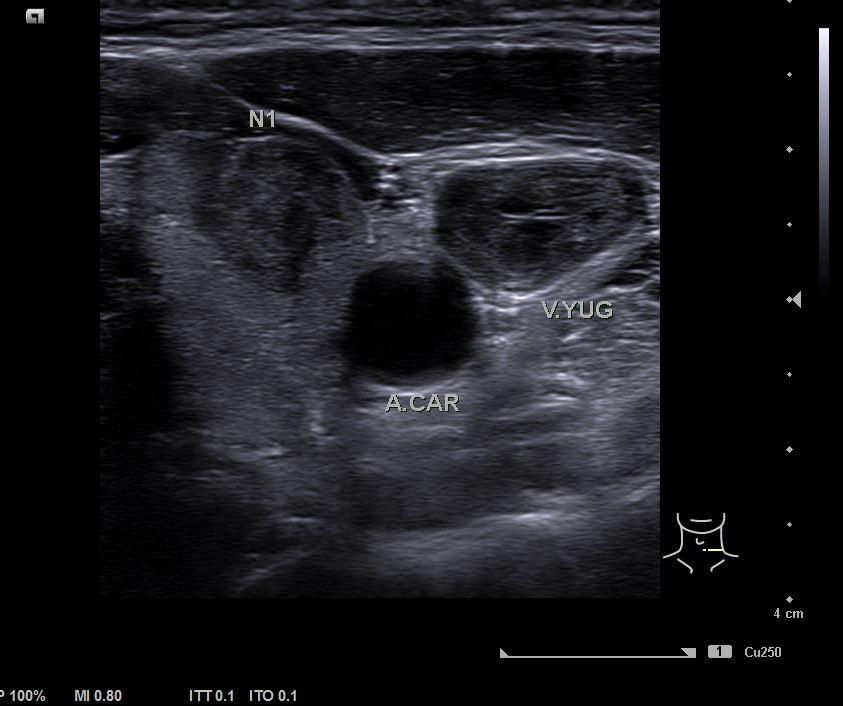

En la ecografía tiroidea se observa en LTI nódulo de 10 mm de bordes mal definidos, lobulado, mayormente sólido, más alto que ancho, isoecogénico, halo periférico hipoecoico, vascularización difusa, que sugiere TIRADS 5. Ausencia de flujo en Vena yugular interna izquierda, ensanchada, que sugiere trombosis yugular aguda o subaguda y junto a ella, posible conglomerado adenopático.